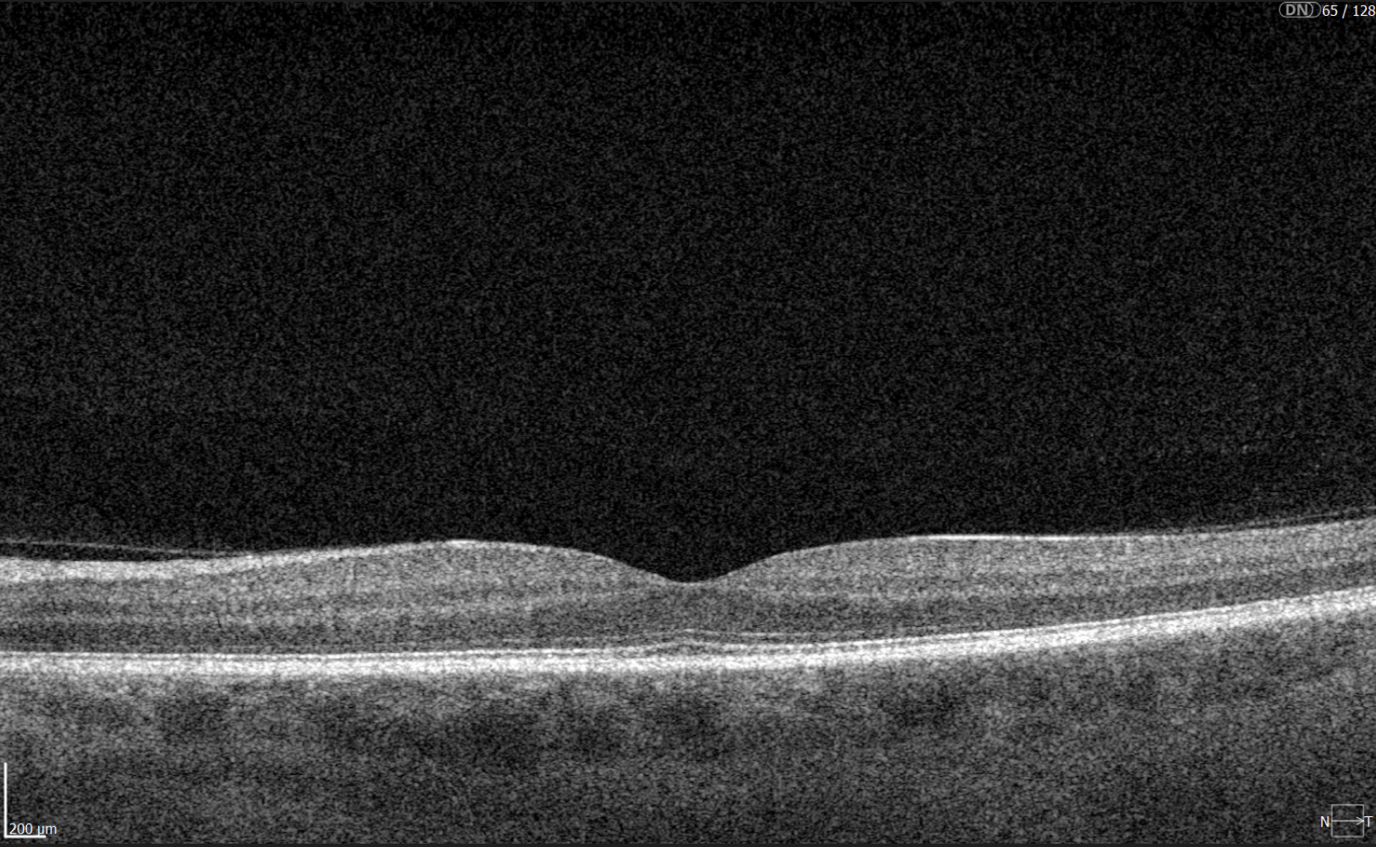

Diabetic retinopathy (hyperreflective foci, moderate destruction of the ellipsoid zone and RPE), diabetic macular edema (neuroepithelium edema, intraretinal cystic cavities), epiretinal membrane What is optimal diabetic retinopathy screening frequency?

Diabetic retinopathy (hyperreflective foci, microaneurysms, destruction of the ellipsoid zone and RPE), diabetic macular edema (neuroepithelial swelling, intraretinal cystic cavities), epiretinal membrane. Monitoring of diabetic retinopathy progression

Diabetic retinopathy (hyperreflective foci, hard exudates), diabetic macular edema (neuroepithelial swelling, intraretinal cystic cavities). OCT red flags in DR progression

Diabetic retinopathy (hyperreflective foci, hard exudates, destruction of the ellipsoid zone and RPE, disorganisation of the retinal inner layers (DRIL)), Diabetic macular edema (neuroepithelial swelling, intraretinal cystic cavities), subretinal fluid. The appearance of these OCT features should prompt clinicians to reconsider therapy, whether by switching anti-VEGF agents, introducing steroids, using combination therapy, or referring patients for surgical evaluation when traction is present.

Diabetic retinopathy (hyperreflective foci, hard exudates, destruction of the RPE), Diabetic macular edema (neuroepithelial swelling, intraretinal cystic cavities), subretinal fluid. What is the best treatment for diabetic retinopathy?